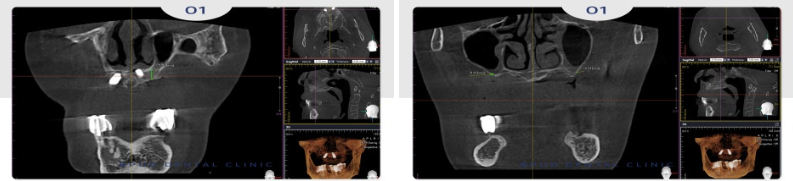

좀 더 정밀한 진단을 위해 3D CT

촬영을 진행하였는데요.

기존 앞니 쪽에 심어져 있는 임플란트 중

하나는 흔들림이 관찰되어 제거를 결정하였고

한 개는 큰 문제가 없어 보이나

사용하기에는 어려움이 있으며

제거 시 치조골 흡수가 일어날 수 있어

잇몸에 묻어두기로 하였습니다.

앞니와 어금니 모두 잇몸뼈가

심하게 흡수되어 1mm도 남지 않아

상악동 거상술과 치조골 이식을 함께

시행하기로 하였습니다.